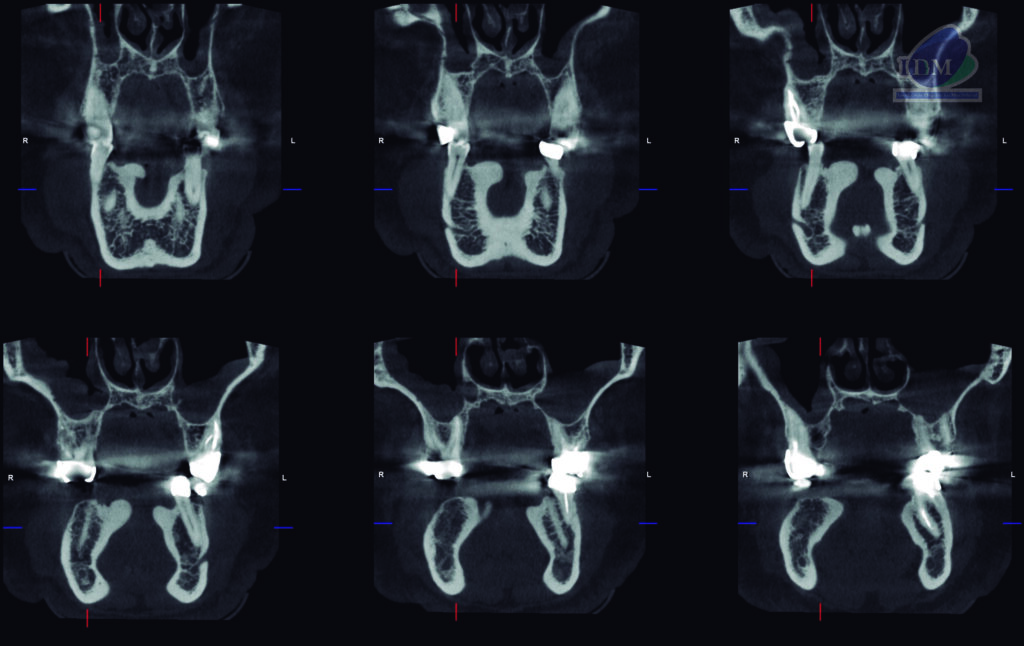

A la evaluación de la tomografía computarizada bimaxilar se observó además de los mencionado, la presencia de imágenes hiperdensas de densidad dentaria de forma irregular ubicadas por lingual, en estrecha relación con la tabla ósea y a nivel de las piezas 34-35 y 44-45 compatibles con torus mandibular.

CORTES CORONALES